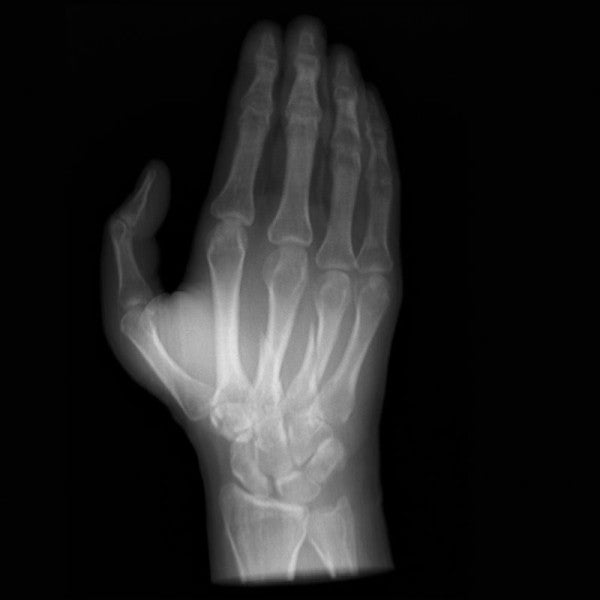

The Anatomy Phantom Models for CT, X-Ray, and Radiation Therapy offer healthcare students an authentic training experience with a non-contrast agent on a model. These anatomy phantom models accurately replicate tissue contrasts, providing a lifelike representation during imaging and radiation sessions.

The anatomy phantom models were created using state-of-the-art technology and are based on actual patient data, ensuring authenticity. They accurately display bones, vessels, and soft tissue with realistic values at 120 kVp tube voltage in CT scans. If used with different tube voltages, such as 100 kVp, the CT values can be adjusted for proper calibration.

The phantom models exhibit realistic tissue contrasts in X-ray imaging, and air spaces are filled with a material measuring approximately -80 Hounsfield units.